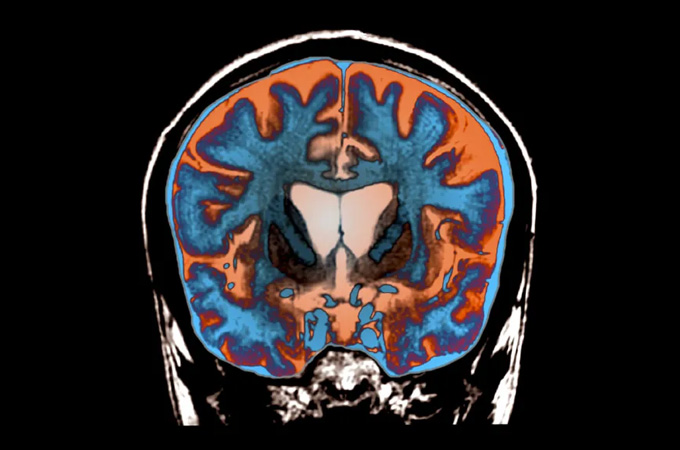

Slowing Huntington’s for the first time

Huntington’s disease is a progressive neurological disorder that steals people’s control over their bodies. Patients may freeze up or involuntarily jerk or writhe. Doctors have no effective treatments, but an experimental drug could change that. The drug consists of a virus carrying tiny bits of RNA that halt the production of disease-causing proteins. Injected into the brain, the treatment slowed Huntington’s progress by up to 75 percent — a triumph for scientists and a promising sign for patients.